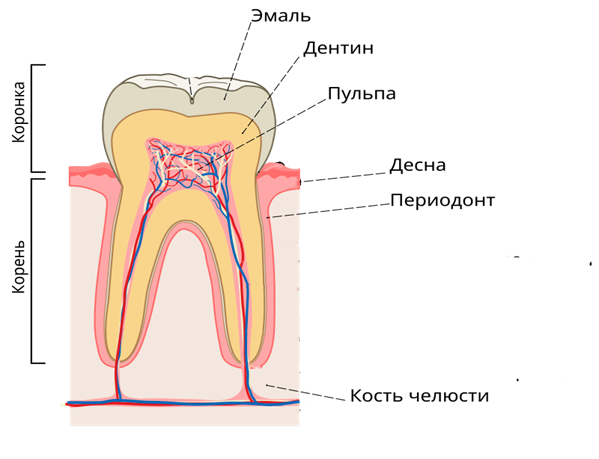

Зуб состоит из двух частей — эмалевой коронки и корня, сделанного из дентина, это такой цемент.

В норме край десны должен находиться там, где заканчивается эмаль. А рецессия — это её смещение ниже соединения коронки с корнем.